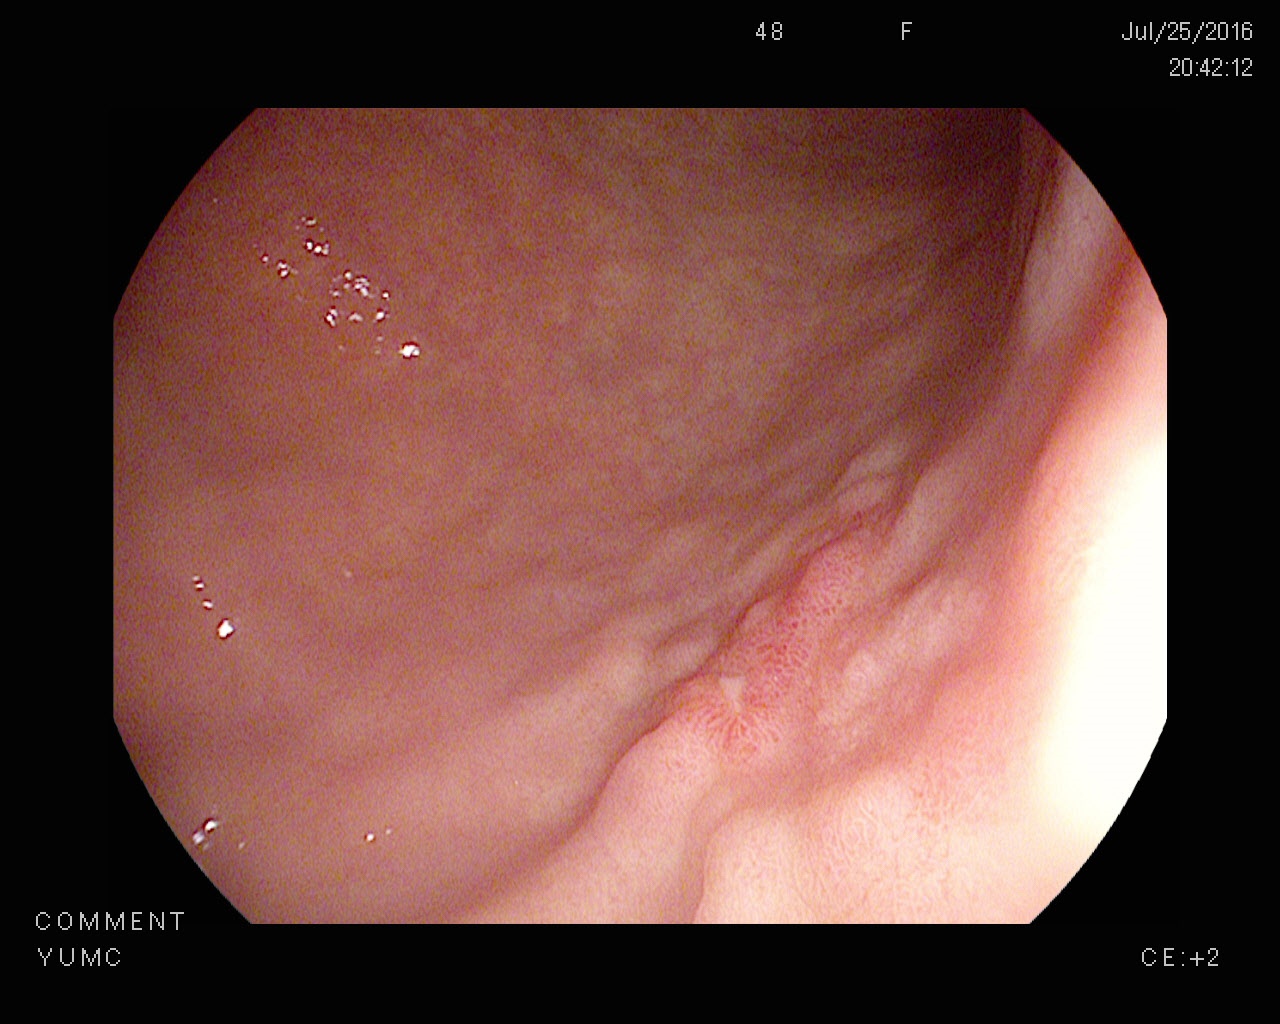

위궤양을 치료받으신 후에도 정기적으로 검진을 받는 것이 필수적입니다. 검진을 통해 궤양의 재발 여부를 체크하고, 적절한 조치를 취할 수 있습니다. 가장 흔히 시행되는 검사는 위내시경을 통한 검사입니다.

내시경을 통해 위의 상태를 직접 확인할 수 있으며, 필요한 경우 생검을 통해 추가적인 진단을 진행할 수 있습니다. 이러한 조치는 위장 질환의 초기 발견과 조기 대응에 중요한 역할을 합니다.